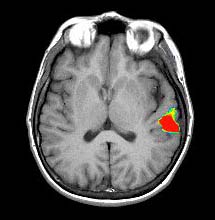

| Images | ![]() | ||||||

| Activation | The left hemisphere shows predominant activation. The following areas were activated: Broca's, left posterior portion of middle and inferior temporal gyri (Brodman's 37), left parietal and left premotor strip. Wide activation is seen in the inferior aspect of the occipital lobes. The main activation on the right is located in the inferior aspect of the frontal lobe (Brodman's 11), a finding consistently seen in this paradigm. |